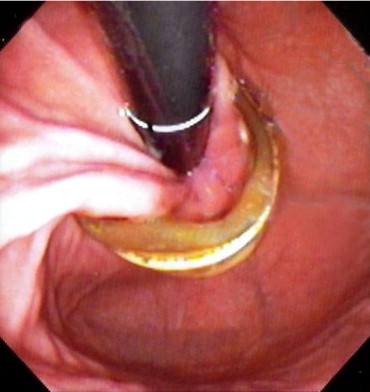

Eroded Lap Band explantation, however, carries a much higher risk profile and in our opinion, should only be done as a stand-alone operation. The University Bariatrics team has extensive experience with these operations and was the first to report & publish the laparoscopic transgastric technique for the removal of eroded bands. We therefore look forward to the opportunity to discuss all of your band removal options with you so that you can decide on the best course of action for yourself!